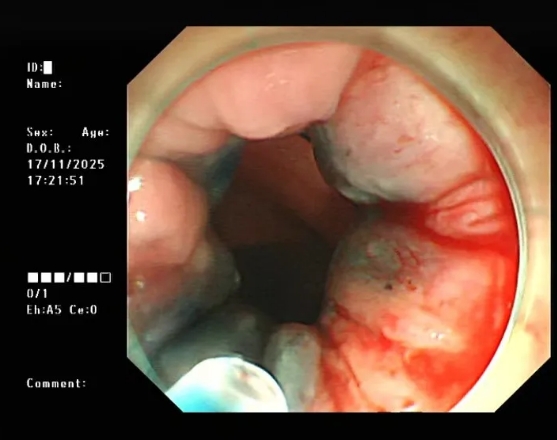

图片

△内镜下硬化治疗